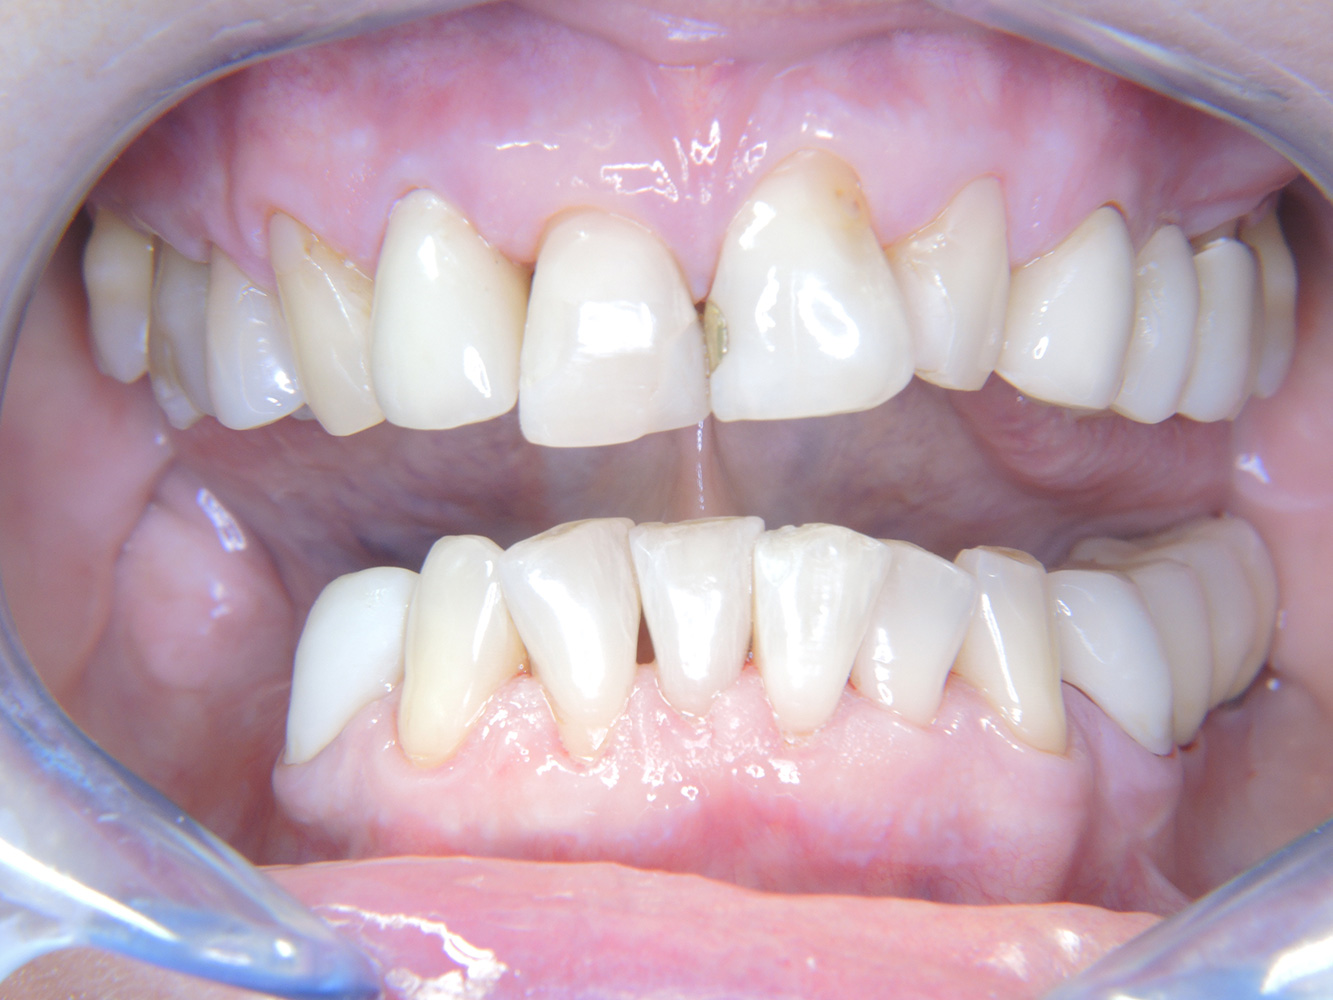

The healthy patient with early periodontal disease*

The 68-year-old patient has no general health conditions and is not taking any medication that may be relevant to her oral health, and her lifestyle does not pose any particular risk. The patient has two dental implants (3rd quadrant, for five years) and a previous case of periodontal disease (stage IV, grade B periodontitis) with tooth loss. Currently the periodontal conditions are stable. However, periodontitis significantly increases the biological complications of implantations and there is a risk of implant loss (21). Four recommendations can be determined for the prophylaxis session.

As the patient does not have any particular risk factors with specific dental implications, the requirements determined from her current state of oral health are crucial. Here, it is recommended that a thorough assessment of periodontal condition be carried out once a year. This will ensure that any potential progression of the previous periodontal disease or development of peri-implantitis can be responded to in good time.

Because the patient has implants and a history of periodontal disease, she is at risk of developing peri-implantitis. It is therefore recommended that she attend a recall session every three to four months.